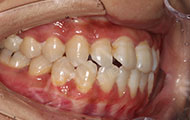

2016年8月8日 到麦芽进行口腔检查

2016年8月8日,经过朋友的劝说,我加入了正畸的行列,我的牙齿上下颌前牙前突咬合不是很好,导致脸型也不是很好看。我对舒适感要求很高,带隐形的完全看不出来。所以选择透明隐形的隐适美。还是私人定制款,嘻嘻。今天来记录我的矫正经历,跟大家一起分享一下,同时给自己留个回忆。我之前就和这边的医生预约好,我很准时的来医院。先是给我拍牙齿的片子,牙齿牙列不齐,幻想着矫牙后的模样~ 相信麦芽的技术!